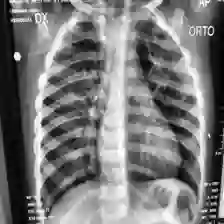

Coronavirus Disease 2019 (COVID-19) demonstrated the need for accurate and fast diagnosis methods for emergent viral diseases. Soon after the emergence of COVID-19, medical practitioners used X-ray and computed tomography (CT) images of patients' lungs to detect COVID-19. Machine learning methods are capable of improving the identification accuracy of COVID-19 in X-ray and CT images, delivering near real-time results, while alleviating the burden on medical practitioners. In this work, we demonstrate the efficacy of a support vector machine (SVM) classifier, trained with a combination of deep convolutional and handcrafted features extracted from X-ray chest scans. We use this combination of features to discriminate between healthy, common pneumonia, and COVID-19 patients. The performance of the combined feature approach is compared with a standard convolutional neural network (CNN) and the SVM trained with handcrafted features. We find that combining the features in our novel framework improves the performance of the classification task compared to the independent application of convolutional and handcrafted features. Specifically, we achieve an accuracy of 0.988 in the classification task with our combined approach compared to 0.963 and 0.983 accuracy for the handcrafted features with SVM and CNN respectively.

翻译:2019年科罗纳病毒疾病(COVID-19)表明需要准确和快速的诊断方法来治疗突发病毒疾病。在COVID-19出现后不久,医疗从业人员就使用X光和计算成的病人肺部透视图像来检测COVID-19。机器学习方法能够提高X光和CT图像中COVID-19的识别准确性,提供近实时结果,同时减轻医疗从业人员的负担。在这项工作中,我们展示了辅助矢量机(SVM)分类器(SVM)的功效,该分类机受过从X光胸部扫描中提取的深层脉冲和手动特征相结合的培训。我们使用这些特征组合来区分健康的、普通的肺炎和COVID-19病人。综合特征方法的性能与标准的脉冲神经神经网络(CNN)和受过手工制作特征培训的SVM相比。我们发现,将我们新框架的特征结合起来,与独立应用脉动和手动特征相比,可以提高分类工作的性能。具体地说,我们实现了0.983和0.983的精确度,与0.983和0.983的S手动方法相结合。